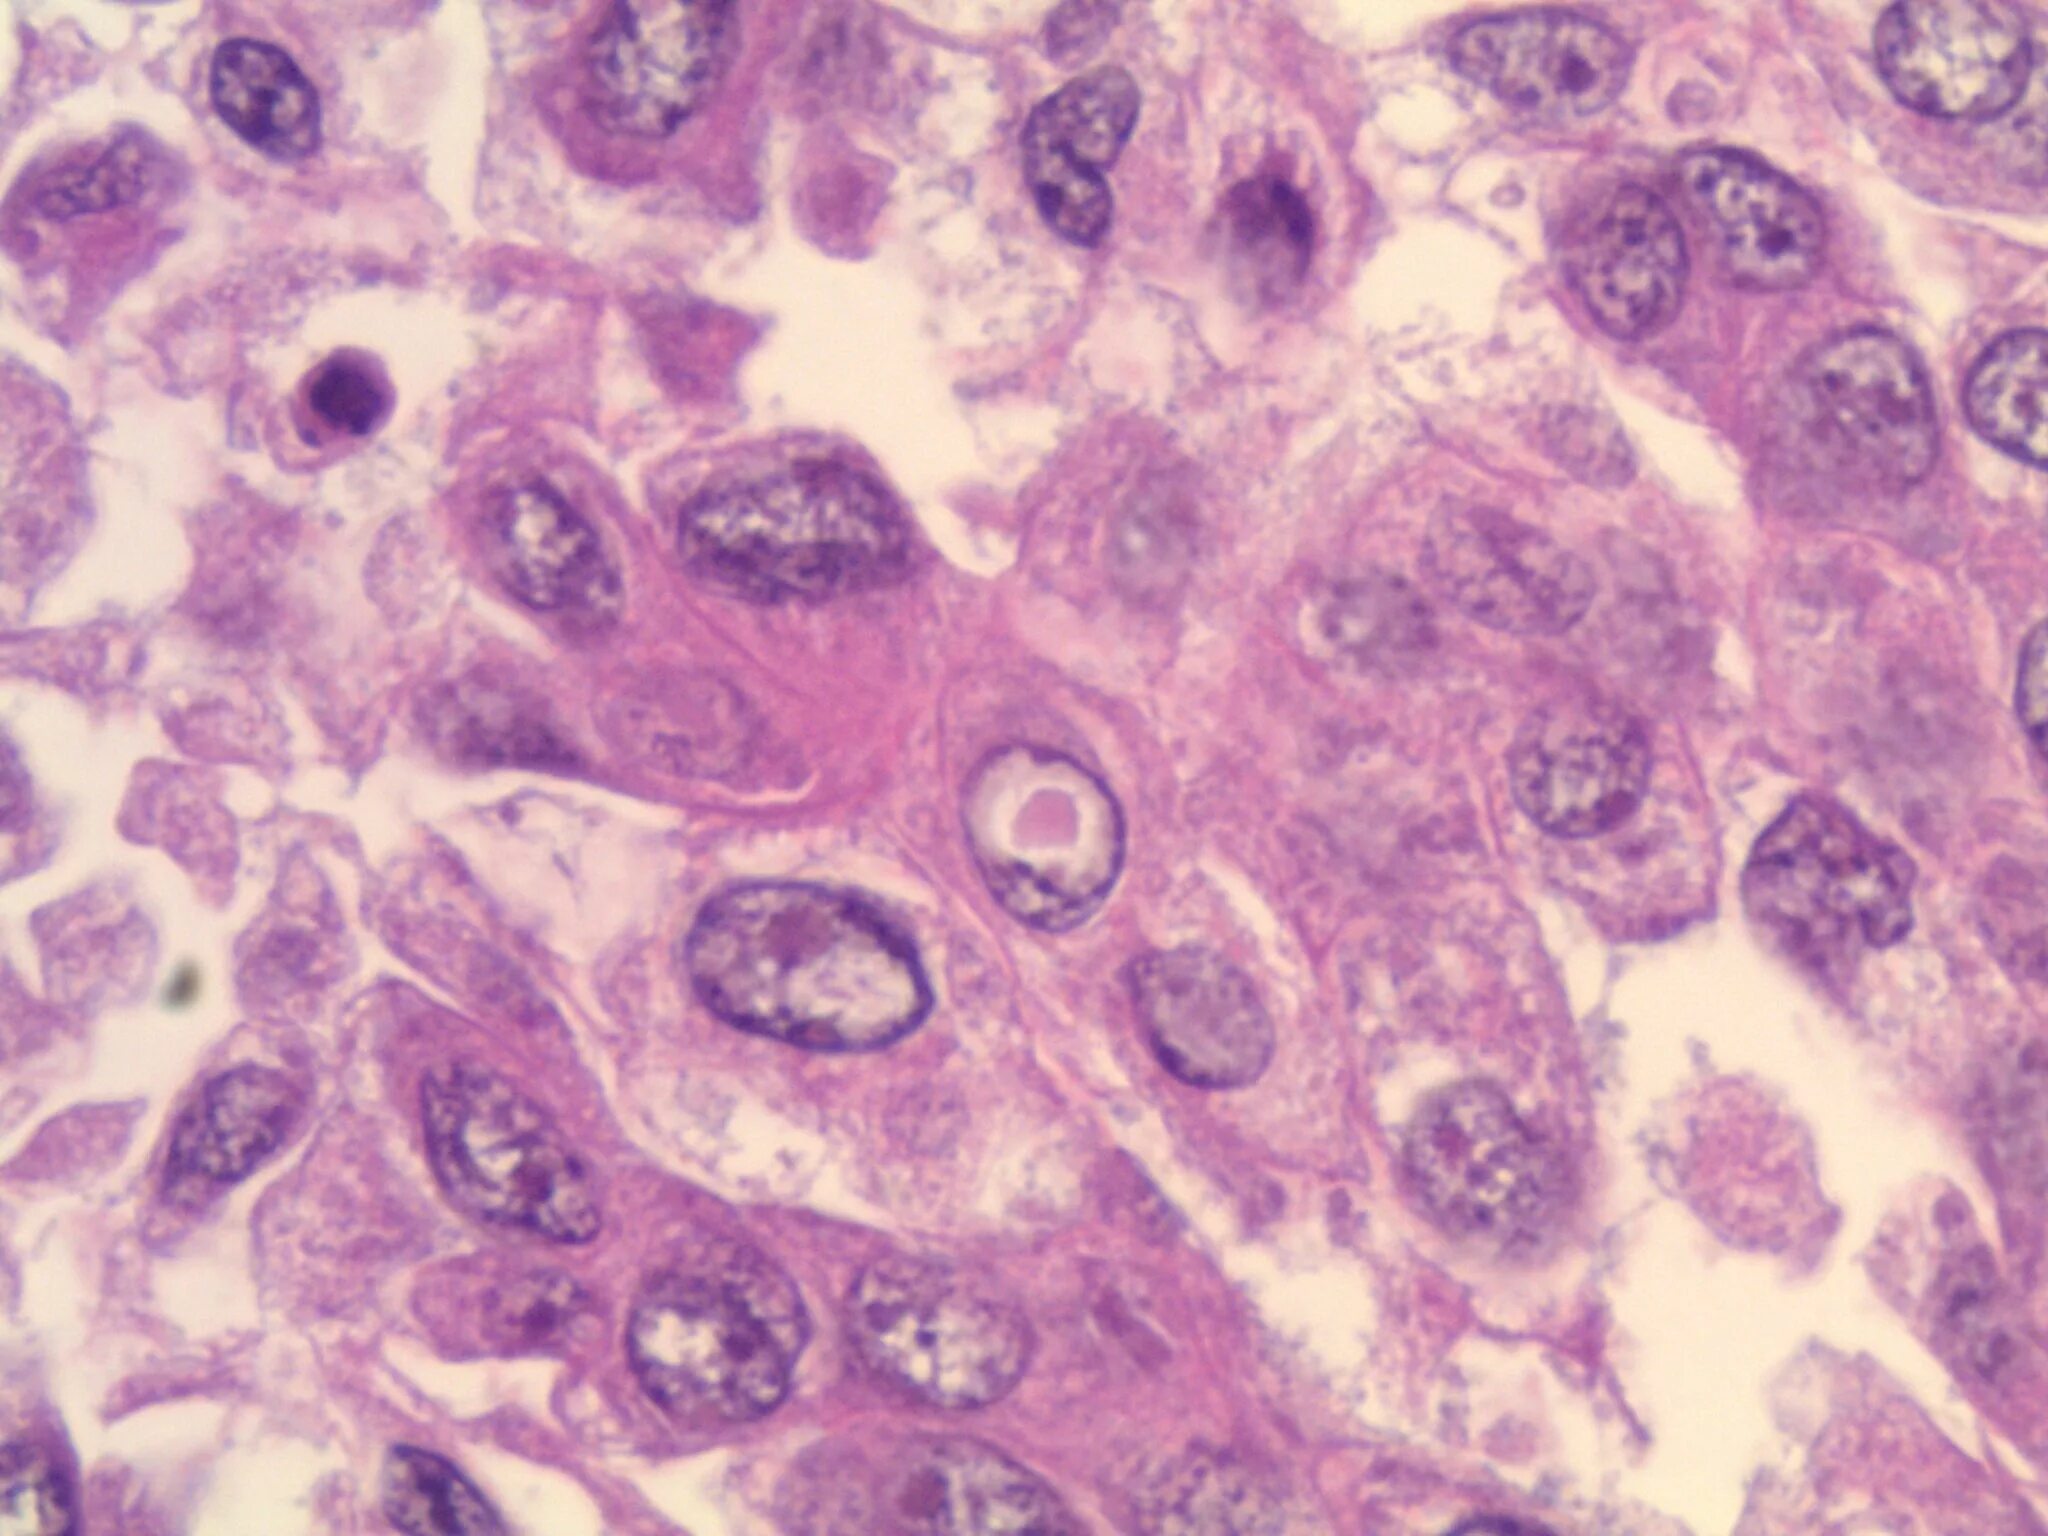

Синусовый гистиоцитоз лимфатического узла